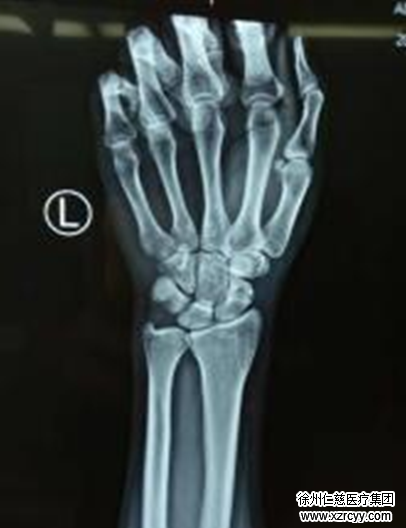

正在值班的手外科二病区齐伟亚主任接待了满头大汗的李先生,通过李先生描述摔倒的情况,齐主任推测是腕舟状骨骨折,而之后的检查情况也证实了齐主任的判断。

齐伟亚介绍,腕舟状骨因其形状细长似舟故得名,而舟状骨骨折是临床常见病,当不小心跌倒,人们总是出于本能手掌触地,导致手腕强度背屈,造成舟骨骨折。外在表现就是伤后局部肿胀,疼痛,腕关节活动受限并疼痛加重。